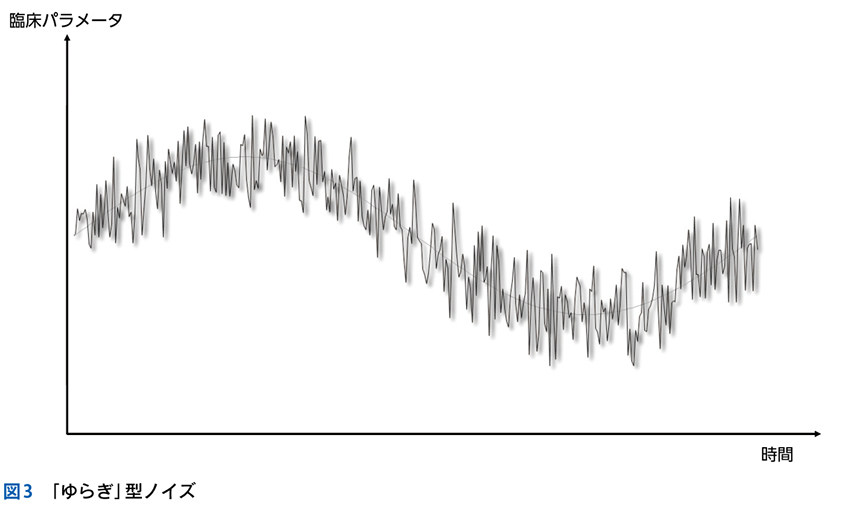

▶ フレームの広さを決めるのは,定義された問題の“yield”である。yieldとは「産み出す」というような意味で,定義された問題がどれほど診断に資するかによって,問題のyieldが高い(high yield),低い(low yield)という使い方をする。high yieldな問題によるフレームは狭く,可能な診断の数を大きく絞り,診断をぐっと近づける。言い換えれば,ある診断(の一群)に対して特異度が高い。一方で,low yieldな問題によるフレームは広く,鑑別診断を意味のある数に絞ることに役立たない(図3)。

▶ 「ノイズ」は,筆者的には臨床推論においてきわめて重要な概念であるため,第4章で詳述するが,フレーミングに関わるのでここで簡単に紹介しよう。ここでは「ノイズ」を,「患者の持つ情報のうち診断と直接的には関連しないもの」を指す語として使用する。対義語(診断と関連する情報)は「シグナル」である。星座のたとえで言えば「シグナル」は星座を構成する星,「ノイズ」は星座を構成しないが近傍にある「くず星」を指す(図4)。